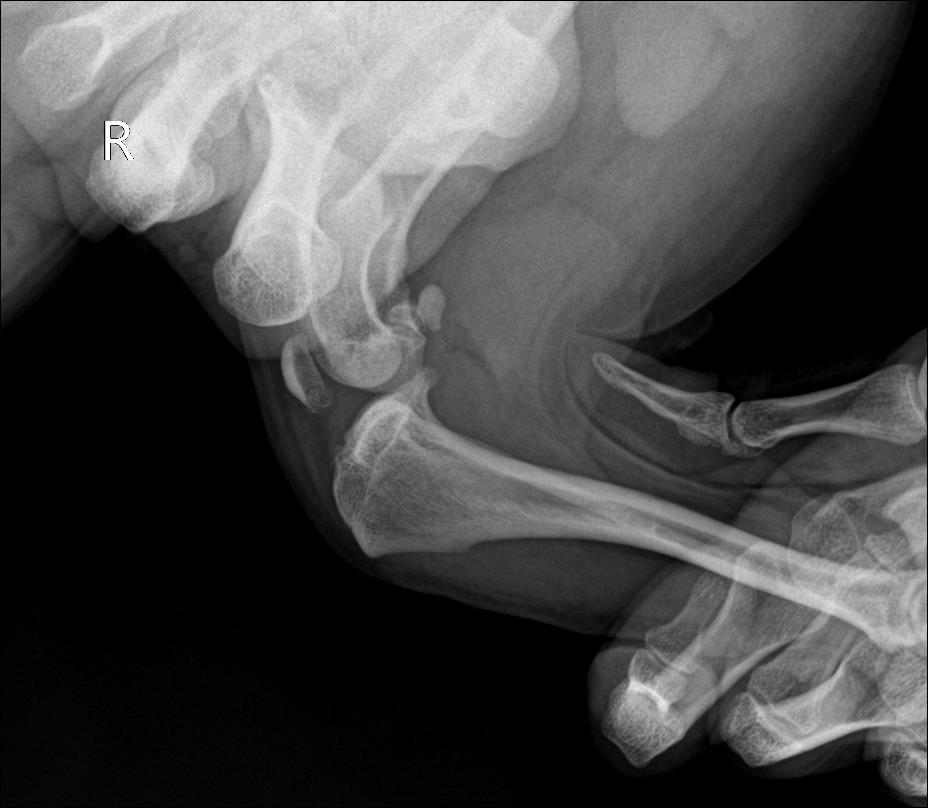

X-ray 검사

십자인대 파열된 우측/ 좌측 방사선 사진 / 출처: 미래동물의료센터

엑스레이 검사상 무릎 관절에서 drawer sign이 관찰되었으며, 십자인대 파열로 진단되었습니다. 처음 내원 당시에는 좌측 십자인대 파열로 진단되어 TPLO 수술을 진행하였고, 수술 후에는 비교적 안정적인 보행 상태를 유지하며 잘 지내던 환자였습니다.

그러나 좌측 TPLO 수술 후 수개월 경과 뒤, 반대쪽인 우측 후지에서 다시 파행이 발생하였고, 검사 결과 우측 십자인대 파열이 확인되어 우측 십자인대 TPLO 수술까지 진행하게 되었습니다.